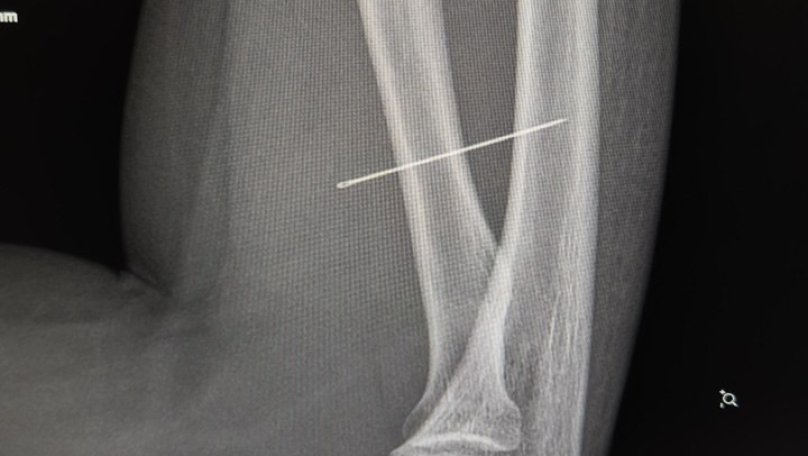

За той тиждень, що Ангеліна проходила з голкою, та просунулася глибше. Вже на рентгені лікарі чітко побачили, що голка зайшла під кутом 45 градусів і застрягла глибоко в товщі м’яза. Якби вона мігрувала ще далі, то могла б пошкодити або судини, або нервові закінчення. Під час операції критично важливим було витягнути голку точно за траєкторією її входження, щоб вона не зламалася. Адже пошук дрібних уламків у м’язах є значно важчим завданням.

За допомогою рентген-навігації ЕОП хірурги точно визначили місце знаходження стороннього тіла, невеликий розріз та правильно і безпечно його вилучили.